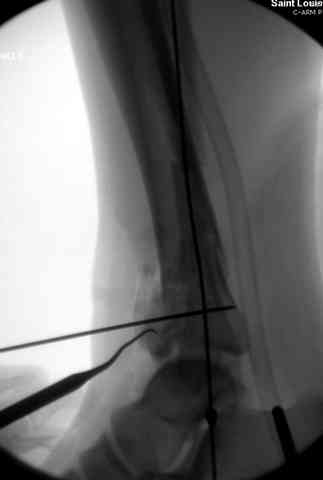

Снова приветствую вас, коллеги. К моменту вступления в обсуждение аксакалов, операция была, увы, выполнена(31.10.07.) Начали с доступа к наружной лодыжке, произвели ее фиксацию спицами, развернули кусок заднего края, наложили дистрактор, затем произвели дистракцию, фиксацию спицами дистального эпиметафиза б/бк,Рентгено-контроль. синтез наружной лодыжки 1/3пластиной. из двух коротких разрезов сформирован канал под медиальную тибиальную пластину LCP. Края ран ушиты без натяжения. Прочувствовать жесткость фиксации винтами с угловой стабильностью не удалось, поэтому дистрактор оставлен на энное время.

На представленных R-снимках не окончательный вид после остеосинтеза. Дистальная опора давила на стопу, пришлось ее сместить проксимально, в рез-те чего, она закрыла щель сустава, последние снимки не информативны.

Дистальные винты как-то чуть не все идут не в дистальные отломки, а в зону перелома. И действительно, присоединяюсь к вопросу Якова - в диафизе так и оставили 1 винт?